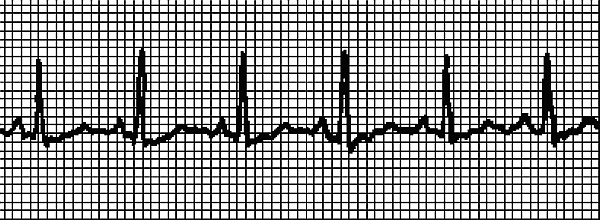

Что надо сделать до приезда врача и после снятия приступа Пароксизмальную тахикардию должен устранить врач. Если нам удастся справиться с приступом до приезда врача – замечательно! Но электрокардиограмма все же необходима, поскольку мы устраним только симптом, и ненадолго. Итак, действия при внезапной тахикардии таковы. • Прежде всего, надо успокоиться, не волноваться, поверить, что сердце надежно выдерживает кратковременную аритмию с ЧСС выше 200 единиц. И немедленно принять 40–50 капель корвалола, или корвалдина, или валокордина. • Несколько раз надавить на глазные яблоки четырьмя пальцами рук: надавливаем и отпускаем, надавливаем и отпускаем, и еще раз, и еще раз. • Медленно плавно и глубоко вдохнуть, затем на 30 секунд задержать дыхание, медленно и плавно выдохнуть. Как диагностируют тахикардию Если после снятия приступа больной решит поскорее забыть о случившемся – это неоправданная беспечность! Тахикардию надо диагностировать, то есть пройти осмотр у врача, сделать ЭКГ и суточный мониторинг по Холтеру (об этом исследовании читайте ниже, в разделе Возбудимость – еще одна функция сердца/Как уловить экстрасистолию ). Врач обязательно назначит клинический и биохимический анализы крови, анализ гормонов щитовидной железы, чтобы исключить или подтвердить «не сердечную» причину тахикардии. Возможно, понадобится пройти ультразвуковое исследование сердца. ЭКГ при тахикардии ... Для проведения электрокардиограммы не требуется никакой специальной подготовки. Но есть 2 рекомендации. 1. ЭКГ проводится после 15–20 минутного отдыха. Придя в поликлинику, не заходите сразу в диагностический кабинет, отдохните, чтобы на результатах кардиограммы не отразилась аритмия, связанная с ходьбой. 2. Перед исследованием не рекомендуется плотный прием пищи. Однако и натощак записывать ЭКГ не надо. На рис. 2 записан нормальный синусовый ритм, на рис. 3 ритм при синусовой тахикардии. ЭКГ записывали у одного и того же человека сначала в состоянии покоя, затем после нагрузки. Даже не имея медицинского образования, можно понять, что существенных изменений в работе сердца не произошло – только учащение сокращений. На рис. 4 записана несинусовая тахикардия. Водитель ритма смещен в предсердие. Если такая тахикардия легко устранится, то причина может быть не связана с болезнью сердца. Врач иногда снимает подобное состояние массажем! Это так называемый массаж каротидного синуса, который проводится в области сонной артерии (καρόω и означает «засыпать», по-гречески). Но без диагностики состояния, без ЭКГ «назначить» массаж нельзя, он не является безобидной процедурой и может нанести вред! Поэтому при пароксизмальной тахикардии ограничимся рекомендацией надавливать на глазные яблоки , которую мы уже приводили. При устойчивой предсердной аритмии можно заподозрить легочную недостаточность или инфаркт миокарда. ![]() Рис. 2. Синусовый ритм ![]()